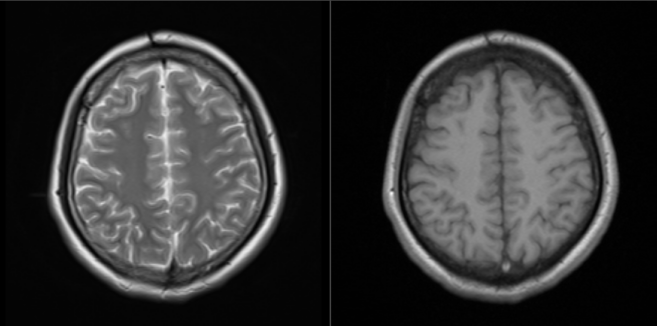

患者男,45岁,以头晕头痛为主诉就诊

图4 PLD=1.5 右侧颞叶血流灌注较对侧减低(红色长箭);PLD=2.5 右侧颞叶血流灌注仍稍减低(红色短箭),表明患者右侧颞叶供血减少,侧枝代偿能力不足,导致右侧颞叶萎缩、外侧裂增宽的病因

图5 PLD=1.5 右侧额顶叶血流灌注减低(红色长箭);PLD=2.5 右侧额顶叶血流灌注显示良好(红色短箭),表明患者右侧额顶叶供血减少,但侧枝循环代偿较好,这是患者右侧额顶叶没有明显异常的原因(文/岳征 河南省中医院磁共振室)